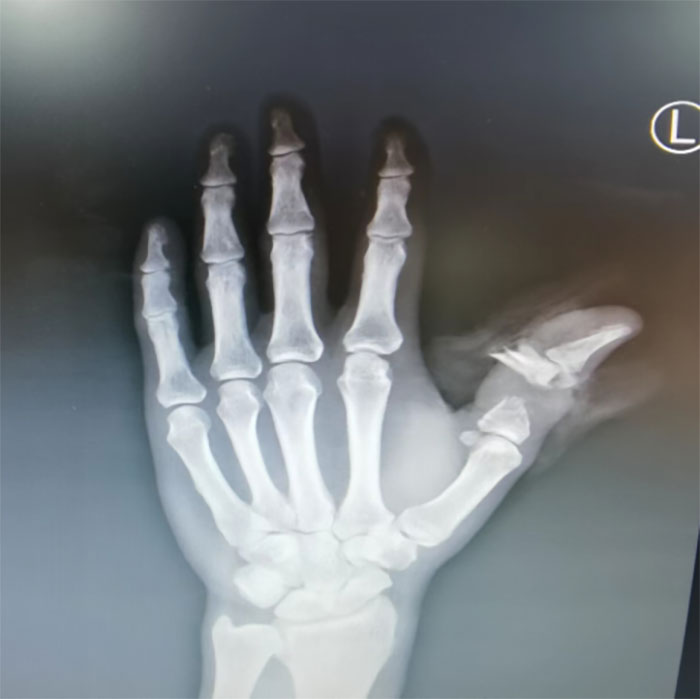

通過(guò)影像學(xué)及查體可見(jiàn)患者左手拇指完全離斷,背側(cè)僅有少許無(wú)生機(jī)皮膚組織相連,指骨縱行劈裂并翻轉(zhuǎn)呈粉碎性骨折,軟組織挫傷嚴(yán)重,可見(jiàn)骨、肌腱、血管及神經(jīng)外露并斷裂,指端無(wú)明顯感覺(jué)及血運(yùn)。